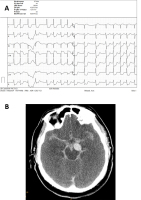

Herz-Kreislaufstillstand - Online-Abbildung 3

Abbildung 3: 50-jähriger Mann mit Laienreanimation bei Herz-Kreislaufstillstand. Bei Eintreffen des Notarztes fand sich Kammerflimmern, das erfolgreich defibrilliert werden konnte. Das EKG bei Klinikaufnahme (A) zeigt eine ausgeprägte Repolarisationsstörung in fast allen Ableitungen mit ST-Streckenhebungen in aVR. Das hochsensitive kardiale Troponin T bei Klinikaufnahme war 71,4 ng/L (Normwert < 14 ng/L). Eine relevante koronare Herzerkrankung wurde in der akut durchgeführten Koronarangiographie ausgeschlossen. Die im Anschluss durchgeführte zerebrale Computertomographie (B) zeigte eine schwere Subarachnoidalblutung aus einem großen Aneurysma der Arteria cerebri posterior sinistra. Die massive zentrale Sympathikusaktivierung im Rahmen der Subarachnoidalblutung führte zu einer sekundären Myokardischämie mit ausgeprägter Repolarisationsstörung im EKG. In unklaren Fällen ist daher eine zerebrale Computertomographie vor einer akuten Koronarangiographie dringend zu empfehlen, um derartige „Fallgruben“ auszuschließen.